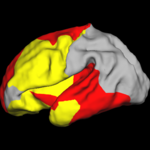

Spherical Demons: Fast Surface RegistrationWe present the fast Spherical Demons algorithm for registering two spherical images. By exploiting spherical vector spline interpolation theory, we show that a large class of regularizers for the modified demons objective function can be efficiently approximated on the sphere using convolution. Based on the one parameter subgroups of diffeomorphisms, More... New: B.T.T. Yeo, M.R. Sabuncu, T. Vercauteren, N. Ayache, B. Fischl and P. Golland. Spherical Demons: Fast Diffeomorphic Landmark-Free Surface Registration. IEEE Transactions on Medical Imaging, 29(3):650-668, 2010.